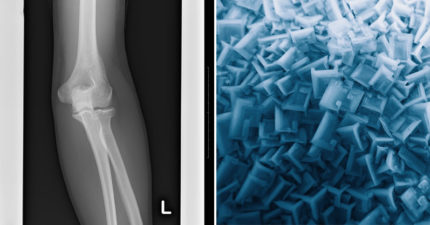

5歲女童「骨齡超前3年」 醫示警避開2物:每天都在用